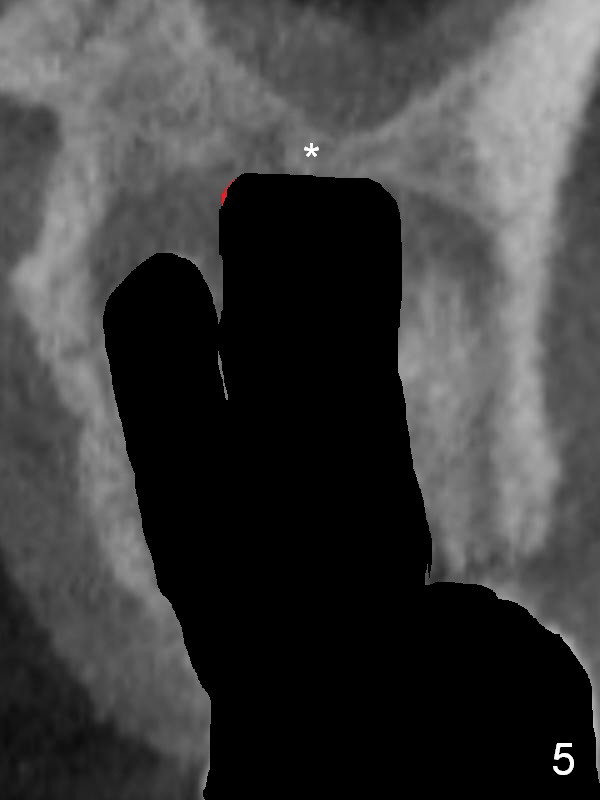

There is purulent discharge from the mesiobuccal fistula (Fig.1 <) during the tooth #14 extraction. Fig.2 is a coronal section of CBCT of the affected tooth showing a large apical lesion (*). When the tooth is removed (Fig.3), limited amount of granulation tissue is removed apical to the palatal root (P in Fig.2). The granulation tissue (Fig.4 red area) above the septum (Fig.3 S) is thoroughly extirpated when the septum is removed (Fig.5 black area).